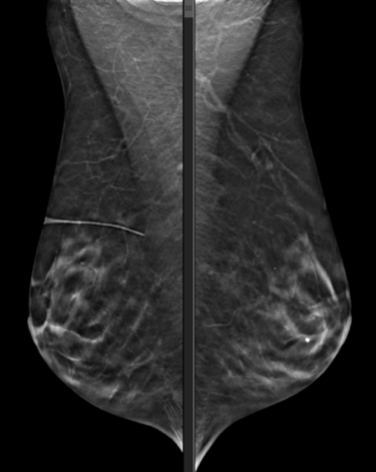

MAMMOGRAPHIE BILATÉRALE EN 3D.

Il existe des calcifications dystrophiques sous-jacentes stables. Dans le sein interne supérieur droit, il y a de nouvelles microcalcifications pléomorphiques, linéaires et ponctuées dans la profondeur moyenne, sans masse associée définie. Ces calcifications ne sont pas visibles sur les mammographies précédentes.

MammoScreen™ : Lésion des tissus mous co-localisée avec calcifications identifiées dans les vues CC DROITE et MLO DROITE avec un MammoScreen Score™ de 9 prenant en charge l’observation.

Avis de mammographie diagnostique de suivi : Il y a des tissus fibroglandulaires dispersés dans les deux seins. Pas de nouvelles masses suspectes. Il y a de nouvelles calcifications dans le quadrant interne supérieur droit. Ils couvrent une surface d’environ 3 cm x 2 cm. Beaucoup de calcifications sont irrégulières. Plusieurs calcifications ramifiées. Les calcifications ont une distribution quelque peu canalaire. Aucune masse ou distorsion associée. Les résultats sont préoccupants pour le DCIS de qualité intermédiaire. L’asymétrie nodulaire et les calcifications ponctuées adjacentes latérales du sein droit sont stables depuis 2012 et sont bénignes.